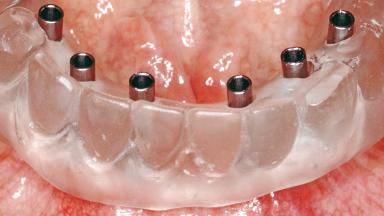

Conventional Loading of Six Implants in the Mandible and Final Restoration with a Full-Arch Metal-Ceramic FDP

# of Implants 6

Type of Implants One-Piece

Attachment One-Piece